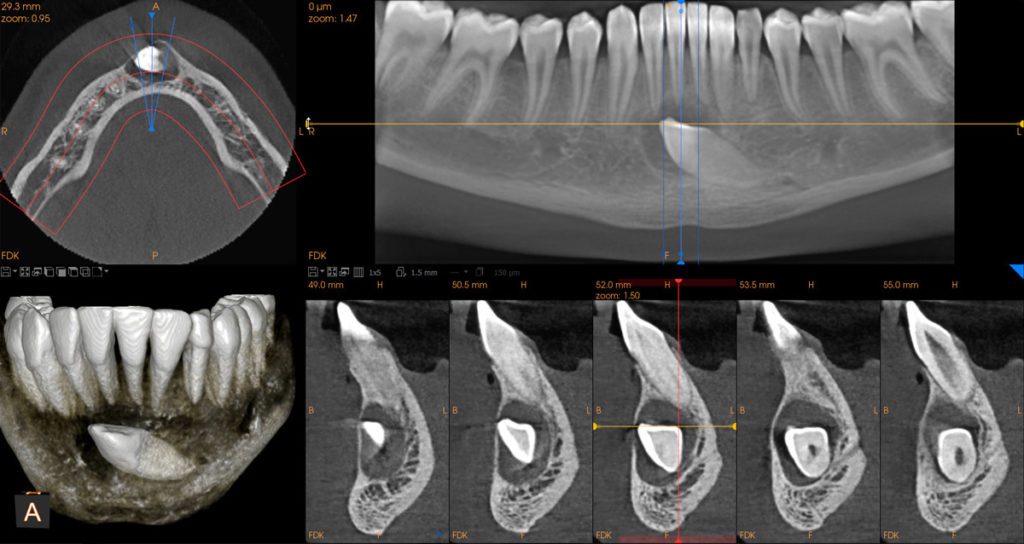

cs9600-8x5_impact-canine

Δημοσιεύθηκε 25 Σεπτεμβρίου 2018 στο 1200 × 638 σε cs9600-8x5_impact-canine